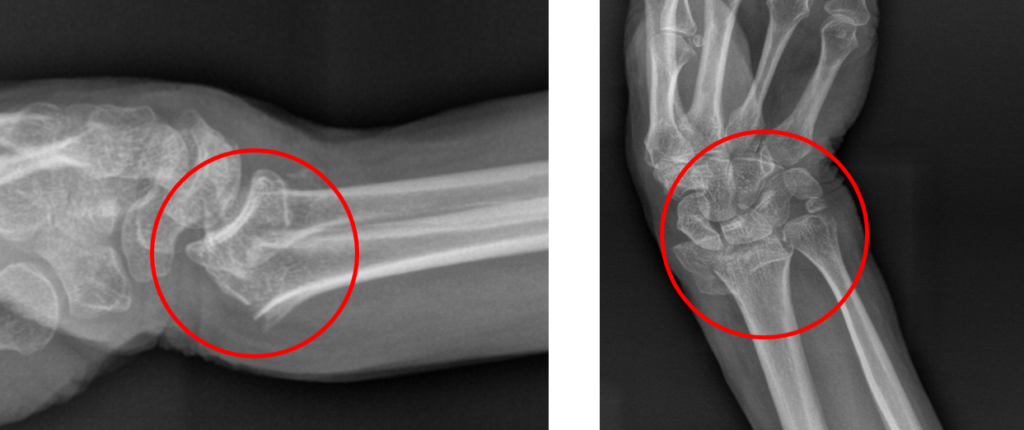

Κατάγματα Πηχεοκαρπικής

Τι Είναι;

Τα κατάγματα αυτά αντιπροσωπεύουν ένα πολύ μεγάλο ποσοστό των

συνολικών καταγμάτων του ανθρωπίνου σώματος και ταυτόχρονα την

πιο συχνή μορφή κατάγματος στην περιοχή του καρπού.

Η διάγνωση γίνεται με απλές ακτινογραφίες στην περιοχή της πηχεοκαρπικής ενώ σε συγκεκριμένες περιπτώσεις μπορεί να χρειαστεί και αξονική τομογραφία με στόχο τον καλύτερο σχεδιασμό μιας πιθανής χειρουργικής επέμβασης.